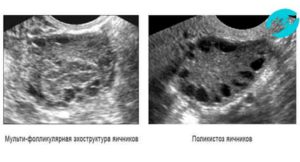

Мультифолликулярные или поликистозные яичники

Иногда очень сложно определить разницу между яичниками поликистозными и мультифолликулярными по результатам УЗИ. Поэтому женщинам, имеющим признаки мультифолликулярных яичников, необходимо динамическое наблюдение у врача-гинеколога с определением гормонального фона.

В норме к моменту овуляции определяется 1-2 доминантных фолликула и несколько антральных. При обнаружении 8-10 пузырьков и более в заключении УЗИ указывается аббревиатура МФЯ.

Мультифолликулярные изменения яичников – это большое количество фолликулов, образующихся однократно или в течение каждого цикла. В норме половые железы включают от 4 до 7 фолликулов.

Когда сонолог обнаруживает 8-10 или больше, он говорит о том, что есть эхопризнаки мультифолликулярных яичников. Большое количество фолликулов может быть вариантом нормы.

Однако в ряде случаев такие УЗ-признаки заставляют врача заподозрить заболевание — синдром поликистозных яичников (СПКЯ).

Это вовсе не одно и то же, хотя на УЗИ эти два состояния очень похожи. Главное отличие в том, что у женщины с мультифолликулярными яичниками без СПКЯ есть овуляция, а месячный цикл регулярный. В этом случае беспокоиться абсолютно не о чем: такое состояние не мешает забеременеть и жить полноценной жизнью.